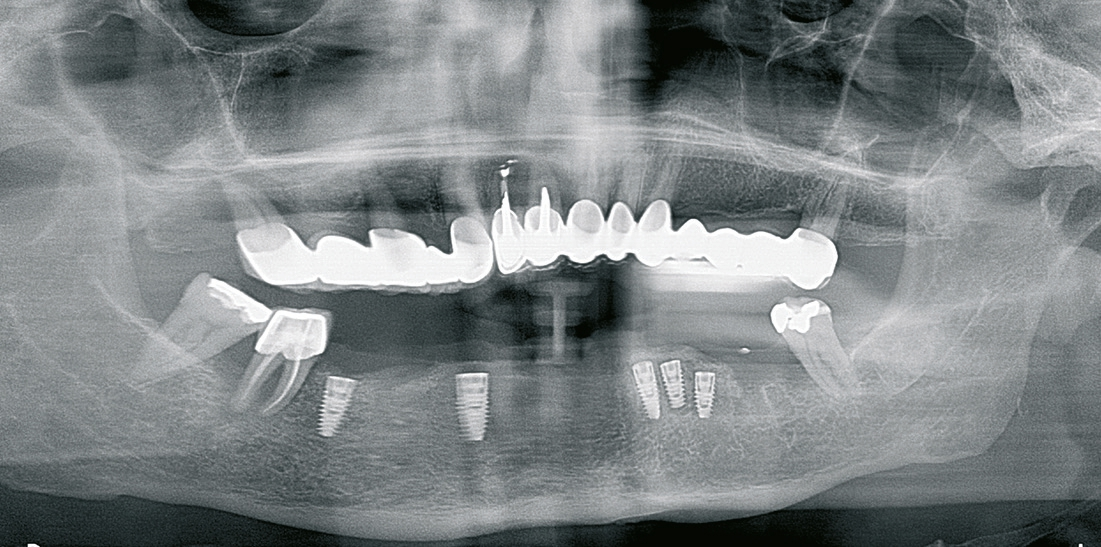

Für die Suprakonstruktionen wurde das Sekundärgerüst auf Abutment-Niveau gefräst. Der Patient bekam im Oberkiefer ein System mit interner Sechskantverbindung (Abb. 9-16). Die Patientin im Unterkiefer bekam ein System desselben Herstellers mit konischer Abutmentverbindung (Abb. 1-8). Davon ist ein Implantat noch in der Einheilphase verloren gegangen. Der betroffene Kiefer konnte trotzdem mit fünf Implantaten versorgt werden. Vom Prinzip „all-on-4“ wurde bewusst Abstand genommen. Ebenso wurde auch auf geneigt gesetzte Implantate verzichtet. Die Implantate, die abgewinkelte Abutments bekamen, wurden nach den prothetisch und anatomisch günstigsten Knochenverhältnissen gesetzt.

Generell zeigen sich verschraubbare Gesamtkieferrekonstruktionen als sehr vorteilhaft. Besonders in Fällen, in den die Gerüste gefräst wurden (Abb. 11), brauchten wir vier Termine und circa drei Wochen bis zur Fertigstellung. 1. Termin: Freilegung, Abdrucknahme, 2. Termin: Abdrucknahme, Kieferrelation, Gesichtsbogenübertragung, 3. Termin: Gerüsteinprobe, Ästhetikaufstellung, 4. Termin: Einsetzen.

Die gesamte prothetische Behandlung dauerte drei bis vier Wochen. Alle Termine waren kurz und entsprechend kurz waren die zahntechnischen Schritte. Die gegossenen Gerüste hingegen waren Material, Kosten und Zeit intensiv. Am geringsten sind die Kosten bei den auf Implantatniveau gefrästen Gerüsten, da die Multiunit-Abutments entfallen. Solche werden allerdings nur für den Oberkiefer ausgewählt. Spannungen wurden hauptsächlich bei den gegossenen Gerüsten festgestellt. Die gefrästen Gerüste haben selten Spannungen und wenn sie beobachtet werden, sind sie durch die Abformung am Stuhl oder die Handhabung der Abutments im Labor bedingt. Die beobachteten Spannungen erschwerten das Einbringen der Konstruktionen bei der Einprobe oder das Einsetzen nicht. Sie wurden festgestellt, indem die Gerüste erst dann passten, wenn alle Schrauben leicht angezogen waren oder bei den Nachkontrollen, wenn einzelne Schrauben gelockert waren. Solche Nachkontrollen sind natürlich wichtig und werden halbjährlich durchgeführt. Sie sind zeitaufwändig, zeigen aber, dass auch bei Schraubenlockerungen, die Patienten niemals etwas bemerkt haben.

Die Gerüste, welche auf Implantatniveau hergestellt wurden, werden überwiegend für den Oberkiefer geplant. Dort empfiehlt sich auch der klassische Sechskant, der leicht gefräst werden kann. Im Unterkiefer führt eine Versteifung des Kiefers durch lange rigide Spannweiten zu Spannungen. Solche Spannungen im Kiefer (Torsionskräfte) kommen bei der Mastikation zustande und auch bei Parafunktionen oder Pressen und können langfristig zu Überbelastungen der Implantate führen. Hier empfehlen sich konische Verbindungen und Multiunit-Abutments. Durch die konische Verbindung ist eine Lockerung des Abutments unwahrscheinlich. Durch die Multiunit-Abutments sind die Torsionskräfte am Unterkiefer ausgeglichen, indem die Verbindung zum Sekundärgerüst als Puffer fungiert (Abb. 4). Sollten diese Kräfte zu hoch werden, lockern sich ein oder zwei Schrauben zwischen Abutment und Prothetik. Es gab nie einen Fall, in dem mehr als zwei von sechs Schrauben locker waren und keinen Fall in dem eine Brücke locker wurde. Kombiniert mit einer Komposit-Verblendung ist diese Lösung für den Unterkiefer optimal. Der Oberkiefer kann, in Fällen in denen beide Kiefer behandelt werden, keramisch verblendet werden.

Die Verblockung aller Implantate miteinander zeigt sehr hohe Stabilität. Das periimplantäre Gewebe ist auch nach vier Jahren stabil. Im Zeitraum der Nachkontrollen gab es keine Implantatverluste. Ähnliche Ergebnisse sehen wir auch bei den all-on-4 Protokollen. Das Setzen von 5-6 Implantaten pro Kiefer erhöht zwar die Kraftverteilung, dient aber primär der Erweiterbarkeit der Versorgung bei potenziellen Verlusten und der optimalen Mastikation dadurch dass alle Gegenkiefer teilbezahnt und implantologisch festsitzend versorgt waren.